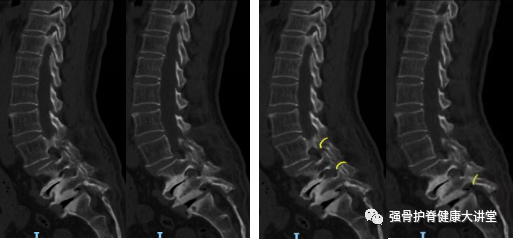

图2

图1、2 为63岁女性,诊断为腰椎峡部裂滑脱(L3-L5),红色线为CT矢状位右侧峡部裂位置,黄色线为CT矢状位左侧峡部裂位置。